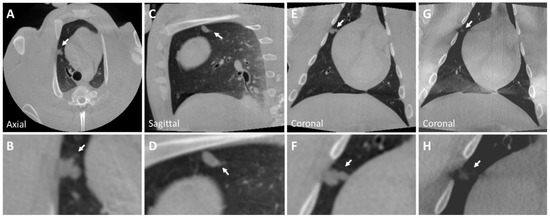

3.2. Post-Mortem Swine Lungs

| Diameter (mm) | CT Attenuation (HU) | |

|---|---|---|

| Lung Nodule | <30 | 50 (30) |

| Nodule 1 | 11 × 6.5 | |

| Nodule 2 | 8 × 7 | −360 (±55) |

| Nodule 3 | 10 × 9 | 25 (20) |

| Nodule 4 | 9 × 8 | −330 (50) |

| Nodule 5 | 16 × 12 | −310 ( |